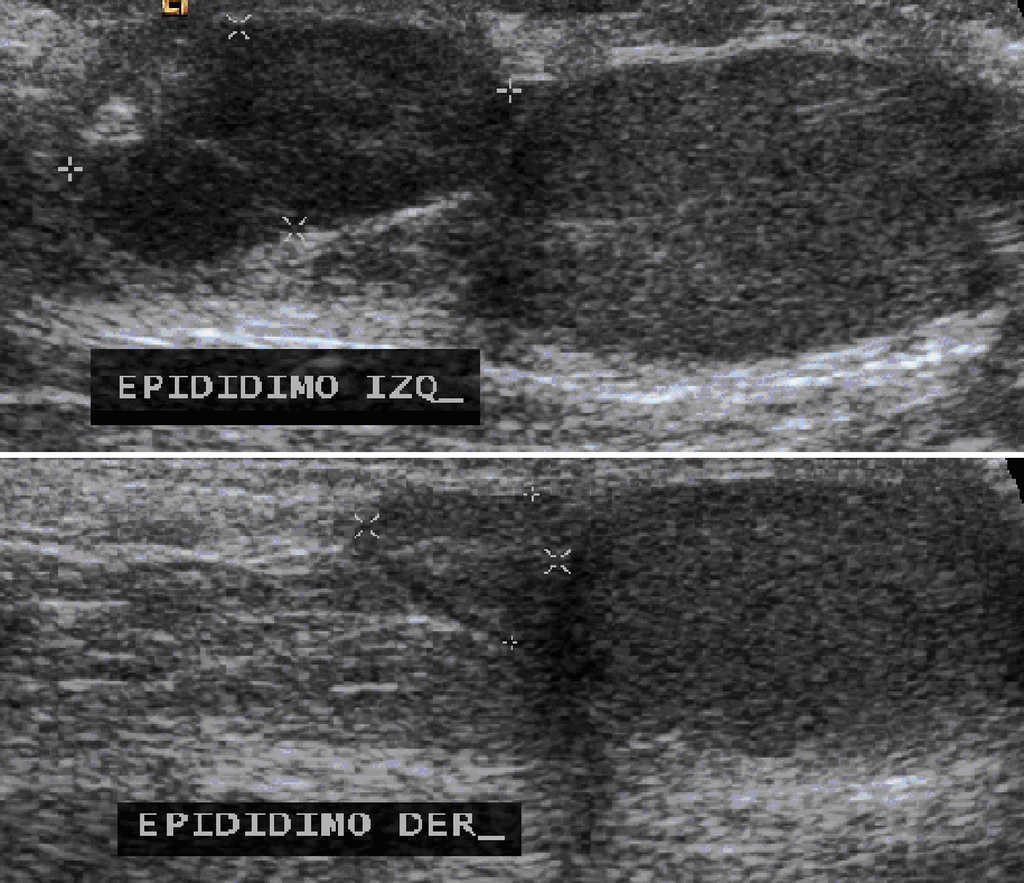

El ultrasonido testicular mostró ambos testículos y epidídimo derecho de tamaño normal, pero el epidídimo izquierdo se observó aumentado de tamaño, de bordes lobulados y bien definidos con dimensiones de 15x7x15 mm y con vascularidad central en la modalidad Doppler (Fig. 4).

Figura 4 Ultrasonido testicular en el que se observa el epidídimo izquierdo aumentado de volumen y el epidídimo derecho normal.